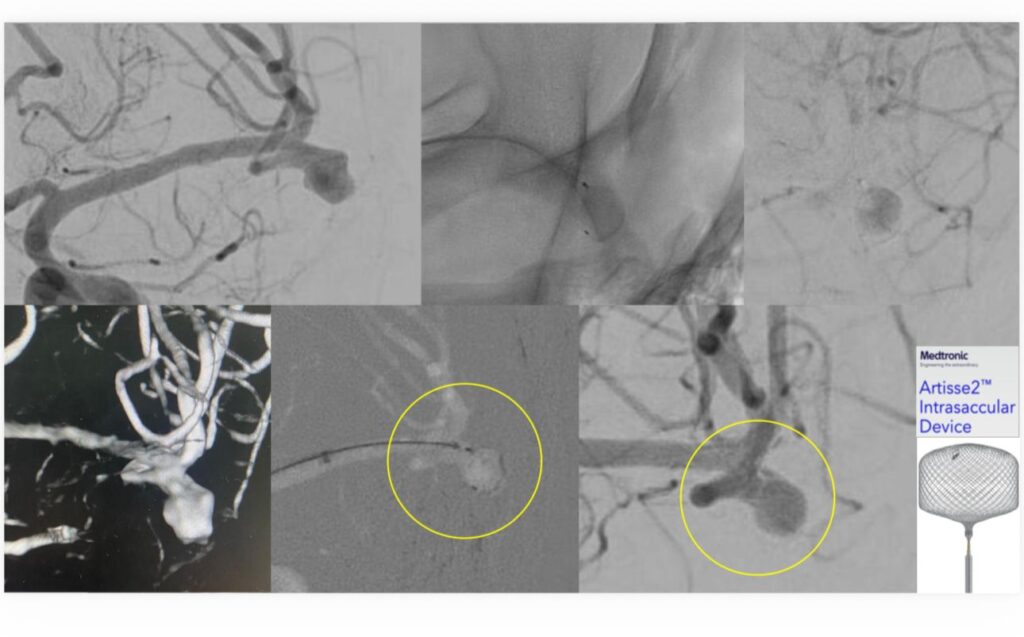

نجح فريق الأشعة العصبية التداخلية في مستشفى الملك فهد الجامعي التابع للمدينة الطبية الأكاديمية بجامعة الإمام عبدالرحمن بن فيصل، في علاج مريض يعاني من تمدد شرياني دماغي واسع العنق، وذلك في أول استخدام سريري لتقنية Artisse™️ في المنطقة الشرقية.

وتمكّن الفريق الطبي من إغلاق التمدد الشرياني بالكامل باستخدام التقنية الحديثة، وخرج المريض من المستشفى وهو بكامل عافيته ، حيث تتميز تقنية Artisse™️ بإمكانية زرع الجهاز داخل التمدد الشرياني بحيث يأخذ شكله بدقة، ما يسهم في تقليل زمن الإجراء وتقليل جرعة الأشعة والصبغة المستخدمة أثناء القسطرة، كما تتيح في كثير من الحالات تجنب استخدام مسيلات الدم بعد الإجراء، الأمر الذي يساعد في تسريع تعافي المريض وعودته إلى حياته اليومية بشكل أسرع.